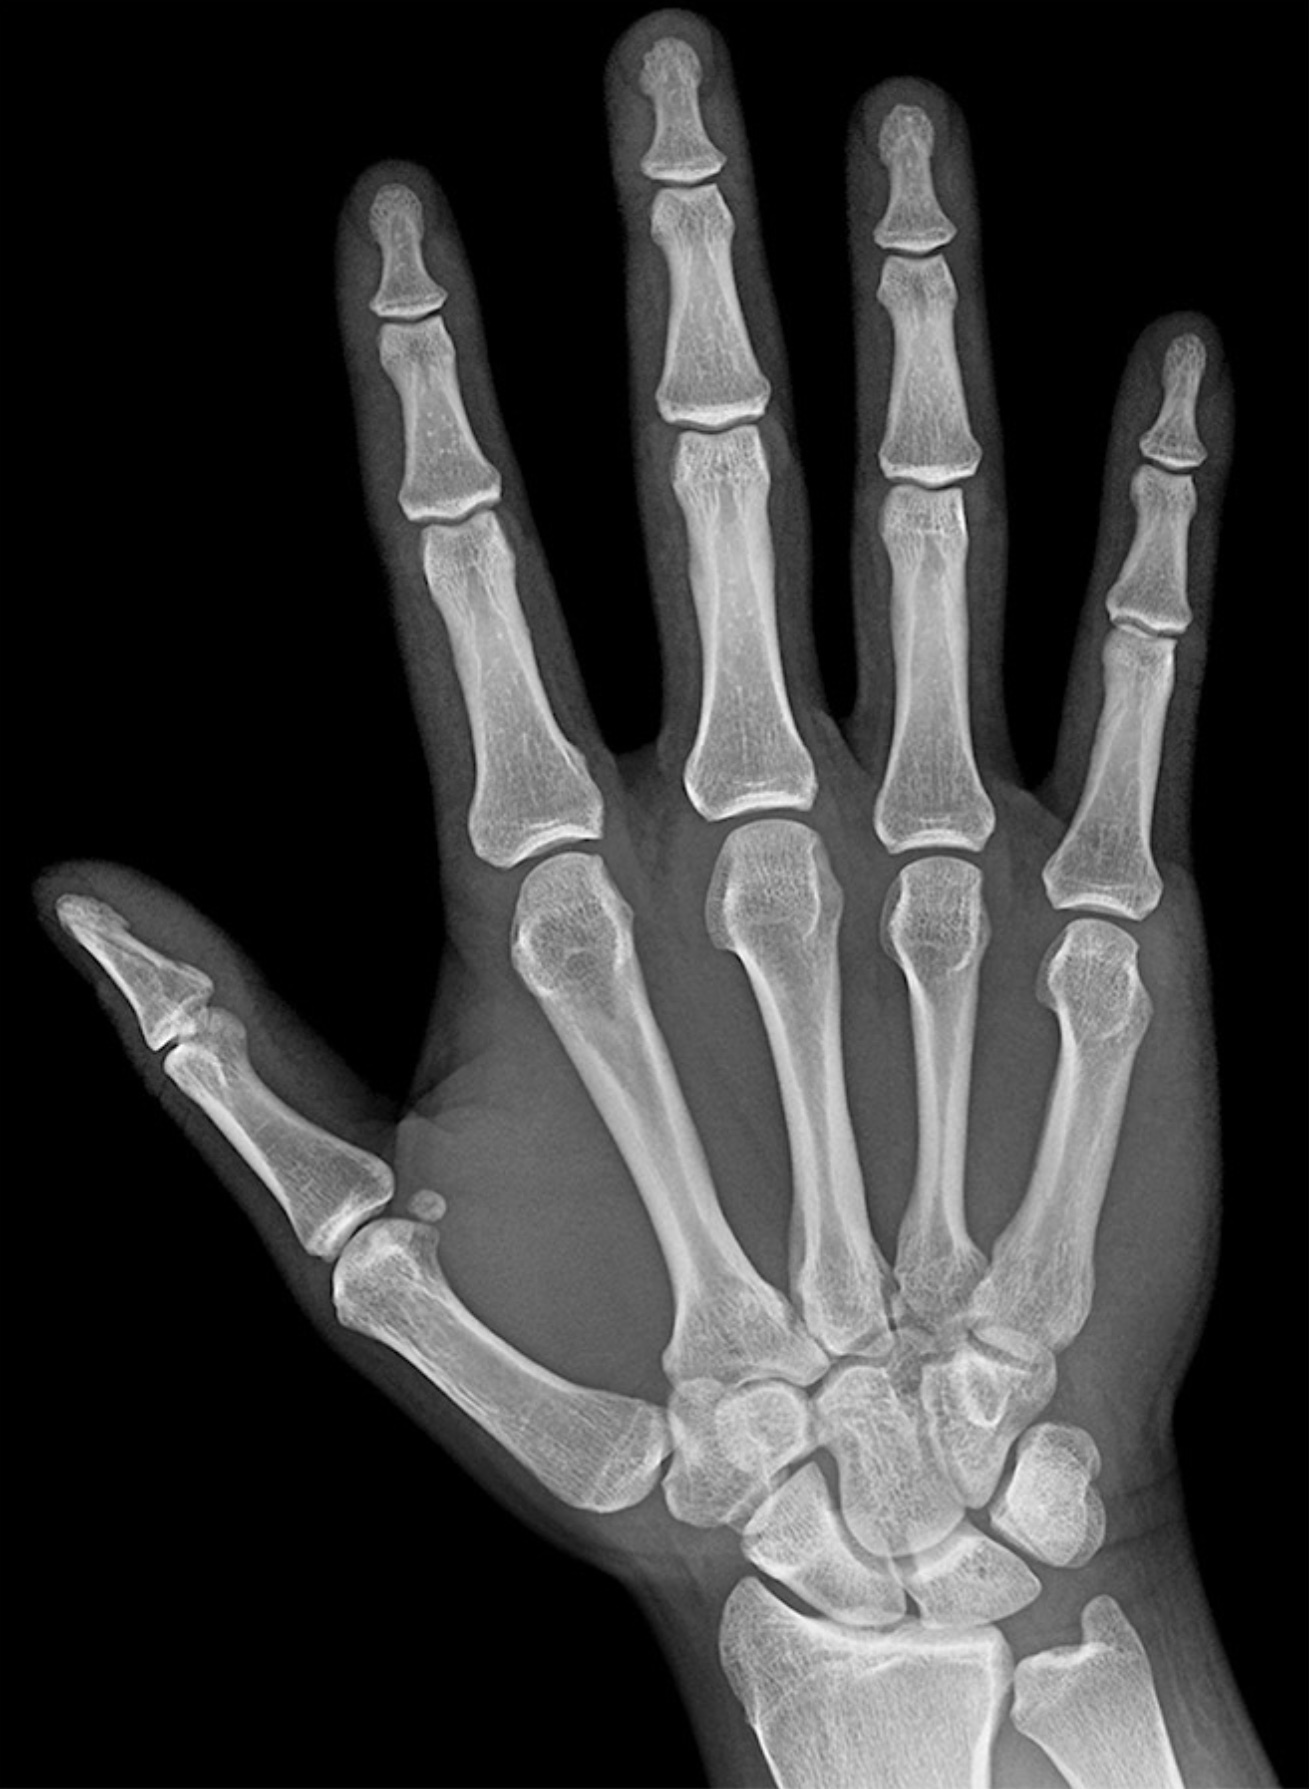

1. 34-yr-old male presents to the clinic with diminished sensation and paresthesia of the medial 1.5 digits. The patient just returned from a long distance cycling race. Describe the anatomy of Guyon’s canal. What major motor deficits would the patient present with for compression of Guyon’s canal? Include in your answer the named branches of the nerve involved and why the patient would be able to perceive sensation for the majority of the dorsum of the hand, but have diminished sensation for the nailbeds of the medial 1.5 digits. (G. Francis)

1. All but five intrinsic muscles of the hand are innervated by the ulnar nerve. (True)

3. Injury to the ulnar nerve within the cubital tunnel causes less clawing of the fingers than does ulnar nerve injury within the ulnar canal (Guyon canal). (True)

4. Injury to the recurrent median nerve, in time, causes the appearance of ape hand. (True)

6. The palmar proper digital nerves supply the dorsum of the fingers at the nail beds. (True)